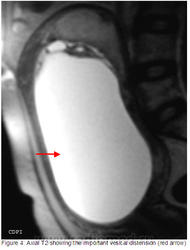

Рисунок 1: